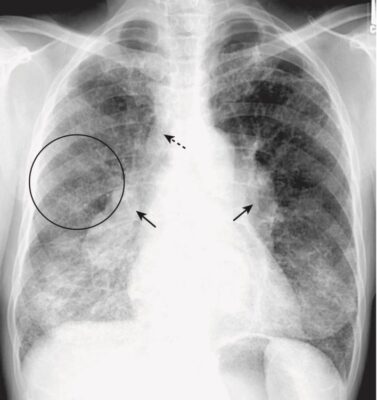

- Phù phế nang phổi cấp tính điển hình thường tạo ra bệnh lý khoang chứa khí hai bên, quanh rốn phổi, đôi khi được mô tả là có hình dạng cánh dơi (bat-wing) hoặc cánh thiên thần (angel-wing) (Hình 6).

- Biểu hiện có thể không đối xứng nhưng thường không chỉ một bên. Phù phổi có nguồn gốc từ tim thường phối hợp với tràn dịch màng phổi và chất dịch làm dày các rãnh lớn và rãnh bé.

- Bởi vì chất dịch không chỉ lấp đầy các khoang chứa khí mà còn cả các phế quản, nên thường không có hình ảnh phế quản chứa khí trong phù phế nang phổi. Thường thì phù phổi hết nhanh sau khi điều trị (<48 giờ).